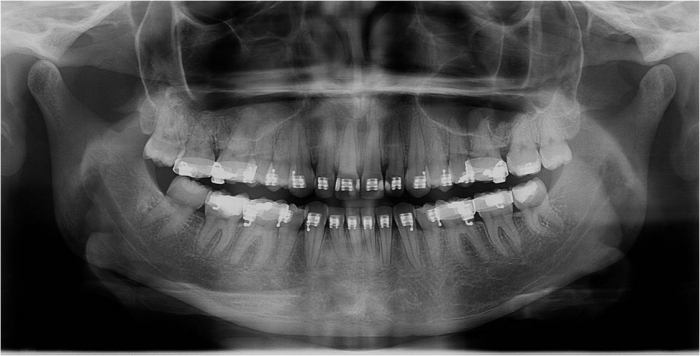

Raio x inicial